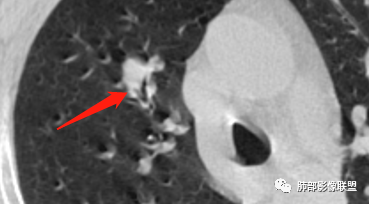

老年男性患者,长期吸烟史,没有呼吸系统临床表现。胸部CT示右肺上叶实性密度结节影,密度均匀,未见空洞及钙化,边缘较光整,未见分叶及毛刺。血管影旁现侧出,支气管进入并截断,不均匀强化。

影像上结节影或块影一旦与支气管密切相关(如截断),不支持硬化性肺细胞瘤、错构瘤、孤立性纤维瘤等良性病灶。如此清晰的边缘也不符合一般意义上的炎性渗出。

赵国千:男性62岁,右肺上叶前段见结节,可见支气管穿行其中,增强轻度强化,倾向良性肿瘤,首先错构瘤、腺瘤;恶性肿瘤,淋巴瘤、淋巴上皮瘤样癌,这个比较难。

冯连彩:老年男性,有吸烟史,因腹疼入院查体发现肺部结节,右肺上叶前段结节,边缘光滑,浅分叶?支气管进入后截断,血管贴边,密度较高,有强化,考虑PSP或炎性假瘤?鉴别淋巴瘤,类癌?

王飞:这里可见支气管阻塞中断,神经内分泌能性大于PSP。